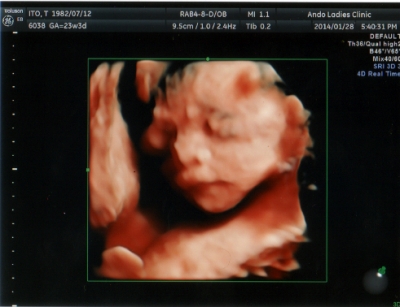

テーマ:赤ちゃん待ち 今日は、初めての4Dエコー!! いつも通っているS総合病院はそっけないし、白黒エコーだとよくわからないしで… 一生に一度だし、4D外来を受診してみようと思い立ちました! 色々検索した結果、職場から近いあんどうレディースクリニックを受診することに。 あらかじめ電話をしての完全予約制です。 4DエコーのDVD録画と写真付きで8,500円になります…。 ちと高いけど、記念ですね♪ で、やってみた感想は…というと 「4Dエコーってすごい!!!やってよかっ...

Pretty Happy | 2014.01.28 Tue 22:18